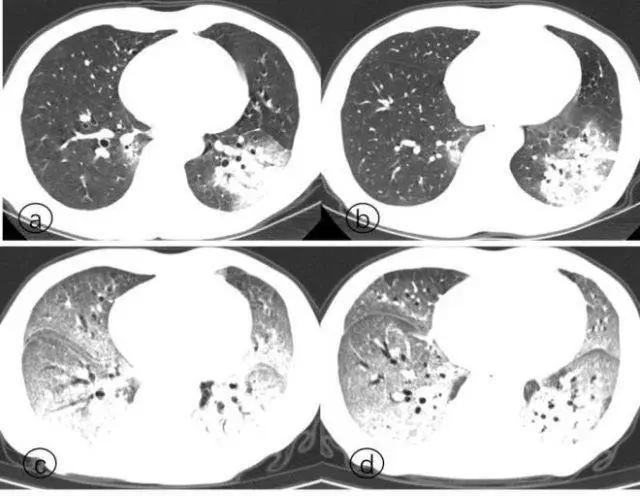

而解剖发现,新冠死者的肺遭到病毒攻击,肺泡损伤,有大量粘稠的分泌物从肺泡里溢出来,CT上看肺变成了一大片白色,医学上叫“白肺”。

患者逐渐演变为白肺的过程